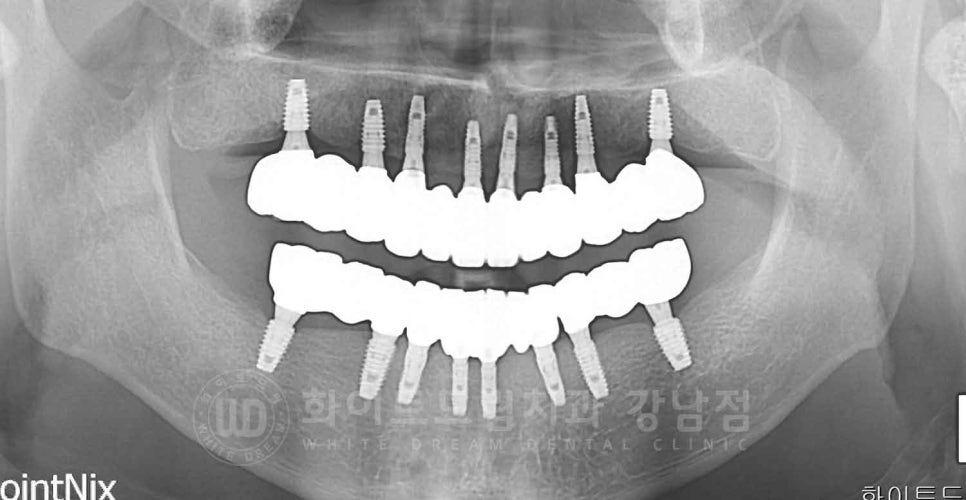

강남역 전악 임플란트 / 치료 후 파노

다행히 환자분은 제작해 놓은 기공물이 잘 맞아

19.09.07 마지막으로 최종 보철을 세팅하고 치료가 종결되었습니다.

강남역 전악 임플란트 사례는 정수윤 대표원장님이 진단부터 수술 및 세팅까지 전담 진료하셨습니다.

임플란트 누적 식립 120,000건에 달하는 수많은 임상 case를 지니고 있는

(24. 5월 기준)